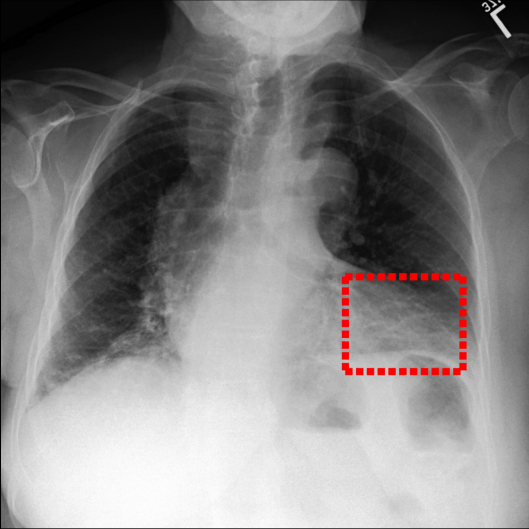

Refer to caption

Figure 4: Visualization of attention maps generated by PLAN on MS-CXR dataset. The red boxes indicate the ground truth for disease localization, while the heatmaps highlight regions with higher activation weights with disease-related phrases in the text.

IV-B1 Phrase Grounding

Phrase grounding associates textual phrases (e.g., disease descriptions or anatomical terms) with corresponding regions in medical images, offering precise diagnostic insights and enhancing model interpretability. Table II presents the phrase grounding results on the MS-CXR dataset. Using the Contrast-to-Noise Ratio (CNR) [27] as the evaluation metric, PLAN achieved the highest CNR across eight disease categories, outperforming MGCA and PRIOR. Heatmaps generated with Grad-CAM (Figure 4) further illustrate PLAN’s ability to accurately localize lesion sites and align disease-related phrases with image regions. Additional comparisons with baseline methods can be found in Figure 5. These findings highlight PLAN’s superior precision and interpretability in phrase grounding tasks.